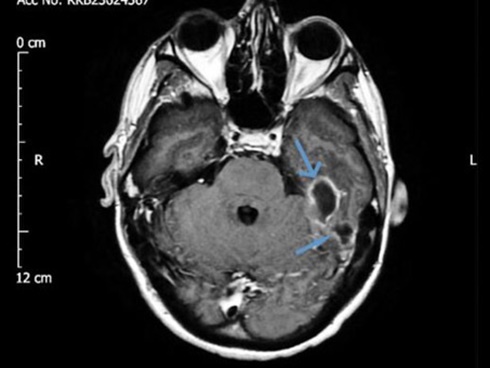

Thật đáng buồn khi tình trạng của bé Evianna nhanh chóng chuyển biến xấu. Rốt cuộc bé được chuyển tới Bệnh viện Nhi Doernbecher ở Portland. Và McCall đau đớn khi nhận được tin dữ: Con gái cô đã bị viêm não và nhiễm trùng huyết - hậu quả của bệnh nhiễm trùng liên cầu khuẩn nhóm B khởi phát muộn.